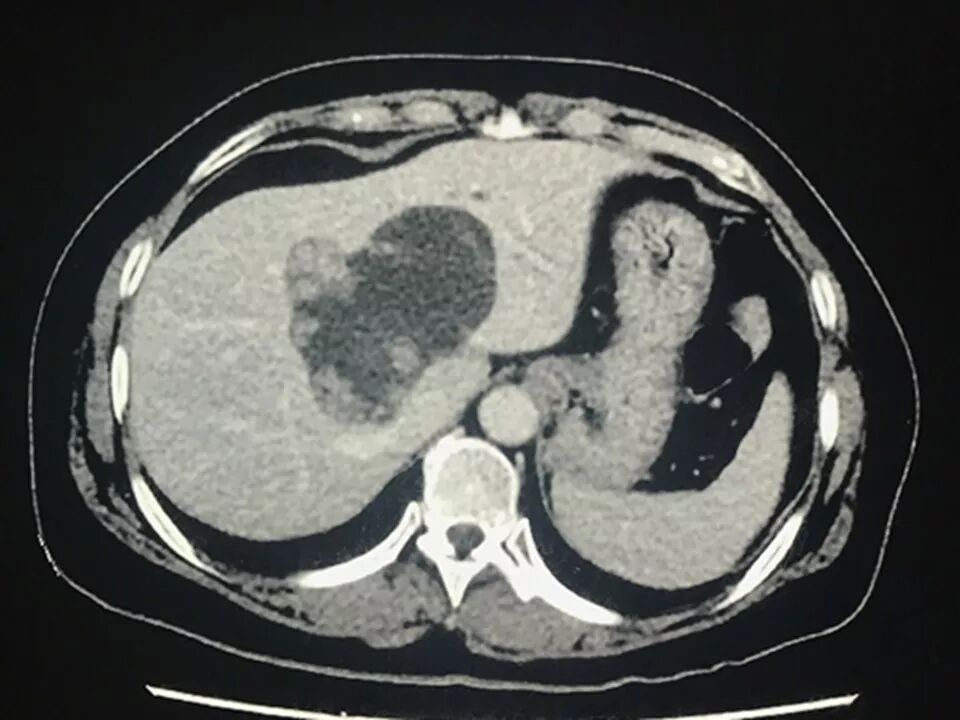

CT表现:

肝内单发占位灶,累及肝左右叶及尾叶。病灶平扫呈低密度,边缘见数枚等密度结节,无钙化,动脉期结节强化,呈等高密度;门脉期结节密度较正常肝实质呈相对稍低密度。